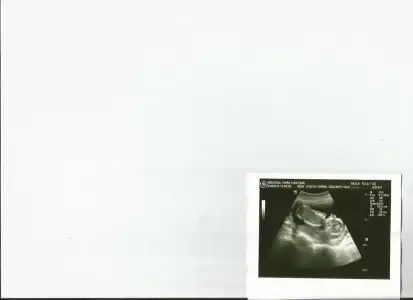

dr soylemeden siz gorun genital nub teorisi ( bebegin cinsiyeti)

Kimler kimler yazdı?Kıza benziyor net goremedim baska foto varmiHadi kızlar,yorum yapacak kimse yok mu?10+2 günlük ultrason fotoğrafı

Kıza benziyor net goremedim baska foto varmi

Bir tane oğlum var ben de kıza benzettim inşallah öyledir bak bir de bu foto var cnm

Kız diyorum çok net belli bu fotosu hayirlisi ogrenince yaz merak ettimBir tane oğlum var ben de kıza benzettim inşallah öyledir bak bir de bu foto var cnm

Kız diyorum çok net belli bu fotosu hayirlisi ogrenince yaz merak ettim

Canim neden erkege benzettin ? Sen kizmi istiyorsun.. bide cok basim agriyo normal mi ?[/QUOTE][QUOTEra53, post: 39559845, member: 254233"]Erkek gibi ama net belli olmuyor hayirlisi olsun masalah kuzuna

Baş agrisi olur bazı gebelerde benim oglum var gonlumden kız geciyor bakalim kiza benziyor dediler bir kac dr gittim hiç biri bacak arasini goremedi yan duruyor mus

Hayırlısı neyse o olsunda canım bilemedim bana da kız gibi geldi dik değil ama bu arada oğlum değil oğullarınBebekim kim bence erkek bebisin kaç haftalik masallah kucagina alirsin inşallah bana erkek gibi geldi netlesince yaz

Kıza benziyor canım hayırlısıyla kucağına almayı nasip etsin rabbim

Canim doktoda erkege benziyo deisti valla dogru tahmin ediyosun ama bana bir daha net aciklarmisin canim dikey ne yatay ne nerden ciziyoz???

Yan duruyor canim kaç haftalik kıza benziyor sankiArkadaşlar ben hiç bişey anlamadım bu fotodan ters mi duruyor yan mı bi anlatsanız????